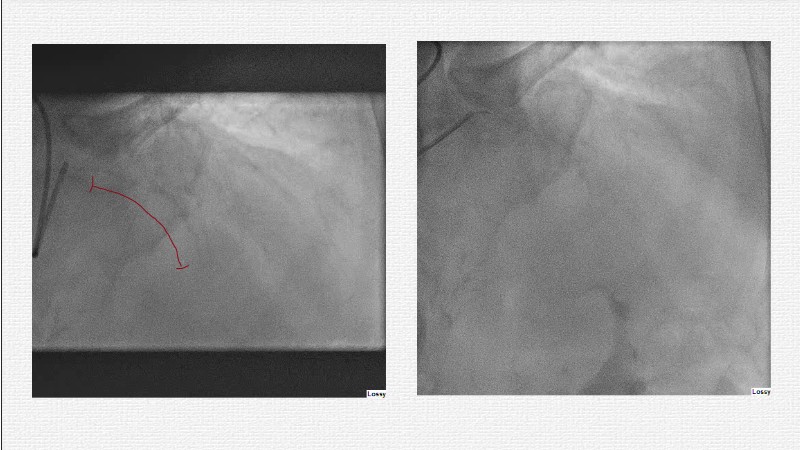

This EuroPCR 2025 session challenges the conventional approach to bifurcation PCI and dissection management. Learn why drug-coated balloons (DCB) may offer better long-term outcomes in cases where stents fall short, how DCBs can simplify bifurcation strategies, and why it’s time to rethink which dissections really need stenting. Through data, case examples, and clear decision-making insights, you'll gain the confidence to broaden your DCB practice where it truly matters.

- To analyse clinical data and use case of drug-coated balloons in bifurcation PCI

- To evaluate which dissection to leave and which to stent